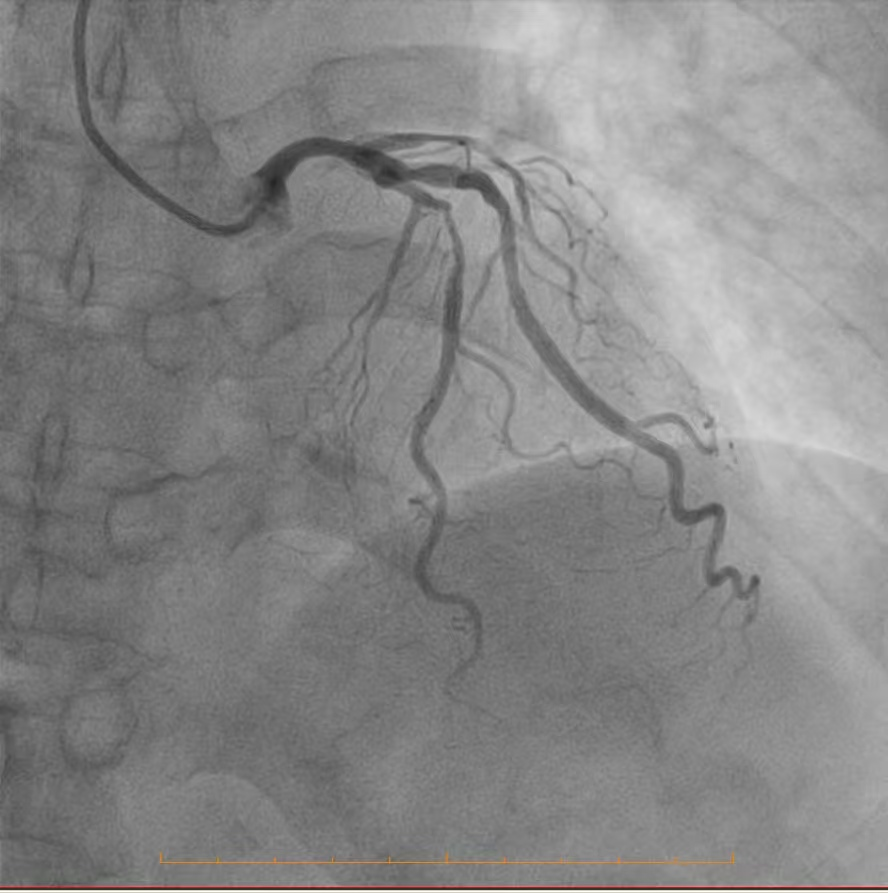

精准研判,明晰战场:冠脉造影揭示严峻挑战

为了制定万无一失的手术方案,必须首先精准“侦察”敌情。团队为患者进行了冠状动脉造影检查,结果清晰地揭示了心脏血管内严峻的形势:造影显示,患者冠脉分布呈右优势型。左主干未见明显异常,这为手术提供了一个相对安全的基础。然而,危机四伏:前降支——心脏最重要的供血血管之一,其近段开口处及以下部位存在约80%的严重狭窄,而中段更是出现了高达90%的极重度狭窄,血流已岌岌可危,是引发严重心绞痛甚至心肌梗死的主要“罪犯血管”。回旋支近段亦存在约60%的狭窄,影响了侧壁的血液供应。情况最为凶险的是右冠脉,其近段有50%的狭窄,而中段以下已经完全闭塞,远段仅能依靠来自左冠脉系统的微弱逆灌注血流勉强维持,这解释了患者为何症状如此严重,生命时刻受到威胁。

冠脉造影影像2